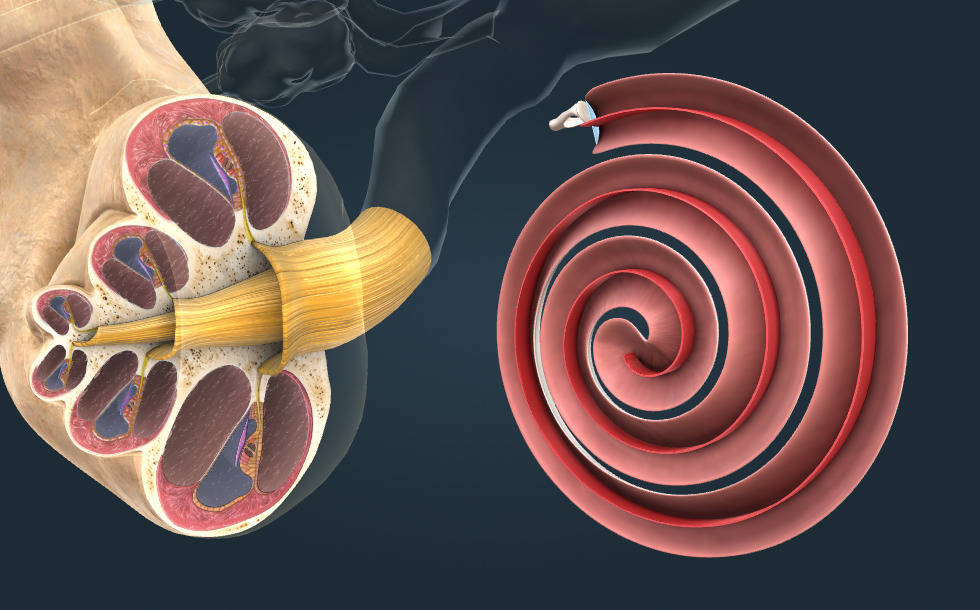

- kulaté okénko - Zakrývá ho membrána pojivové tkáně. Vibrace se šíří v tekutině bubínkového kanálu směrem ke kulatému okínku. Kulaté okno je "výstupem" z hlemýždě.

- oválné okénko - Zakrývá ho membrána z pojivové tkáně, tzv. oválná membrána. Vibrace třmínku se přes membránu přenese do tekutiny vestibulárního kanálu. Oválné okénko je "vstupem" do hlemýždě.

Tonotopie

A helyelv szerint a hangmagasságot az határozza meg, hogy a belső fül csigájában hol jön létre a legnagyobb rezgés az alaphártyán. A nagyobb frekvenciájú rezgések, amelyek a magasabb hang hatására alakulnak ki, a csiga alapjához közel elnyelődnek, és rezgésbe hozzák az alaphártyát. A mélyebb hangok hatására létrejövő kisebb frekvenciájú rezgések a csiga csúcsához közelebb rezgetik meg az alaphártyát. Az elnyelődés helyén elektromos ingerület alakul ki, ami az agyba jut. Így az ingerület keletkezésének helye kódolja a hang magasságát.

Békésy György (1899–1972) magyar-amerikai biofizikus kísérletekkel igazolta ezt az elméletet. Felfedezéseivel alapvetően járult hozzá a hallás mechanizmusának megértéséhez. 1961-ben „a belső fül, a csiga ingerlésének fizikai mechanizmusával kapcsolatos felfedezéseiért” orvostudományi Nobel-díjat kapott.

Spodek třmínku je přizpůsoben oválnému okénku hlemýždě. Bazilární membrána je umístěna uvnitř hlemýždě, vede podél špičky hlemýždě, kde se otočí a pokračuje v Reissnerově membráně. Membrána rozděluje hlemýždě na 3 dutiny: vestibulární, hlemýžďový a bubínkový kanál.

Hlemýžď je naplněn tekutinou, která se rozkmitá pomocí třmínku. Vibrace s vyšší frekvencí, které vznikají při vyšším zvuku, jsou pohlceny na spodku hlemýždě a rozvibrují bazilární membránu. Vibrace s nižší frekvencí vytvářejí hluboké zvuky a rozvibrují bazilární membránu na vrchu hlemýždě. Když dojde k pohlcení vibrace, vytváří se elektrický signál, který je přenášen do mozku. Vznik elektrického signálu, který je kódován na místě pohlcení, se nazývá tonotopie.